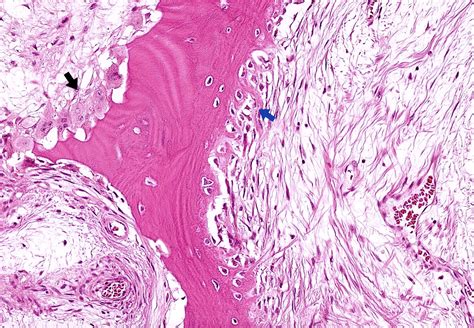

Understanding Bone Health Online Course - Key Clinical Skills